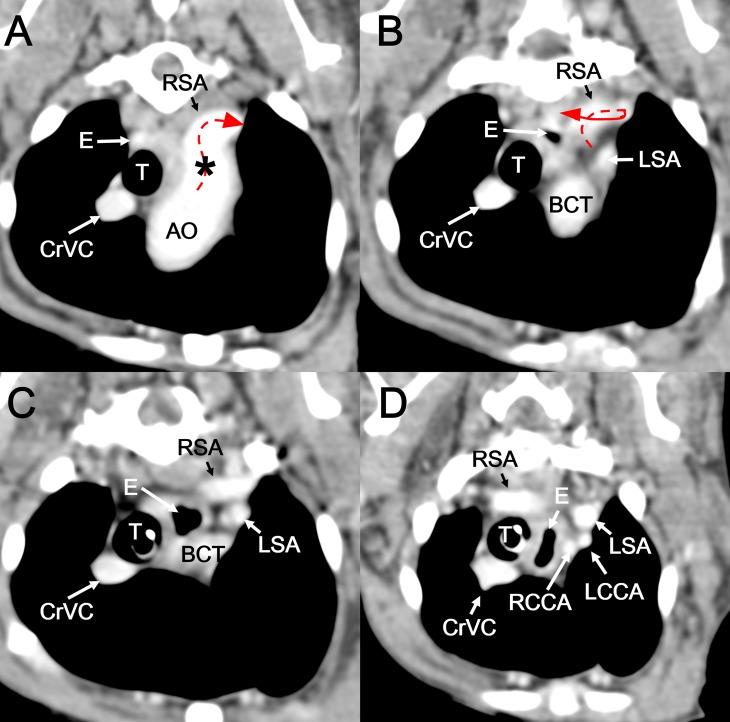

Computed tomography angiography reveals stenosis and aneurysmal dilation of an aberrant right subclavian artery causing systemic blood pressure misreading in an old Pekinese dog.

A 14-year-old dog weighing 4 kg presented with hypotension only in the right forelimb. Thoracic radiography revealed a round soft tissue opacity near the aortic arch and below the second thoracic vertebra on a lateral view. Three-dimensional computed tomography angiography clearly revealed stenosis and aneurysmal dilation of an aberrant right subclavian artery. Stenosis and aneurysm of an aberrant subclavian artery should be included as a differential diagnosis in dogs showing a round soft tissue opacity near the aortic arch and below the thoracic vertebra on the lateral thoracic radiograph.